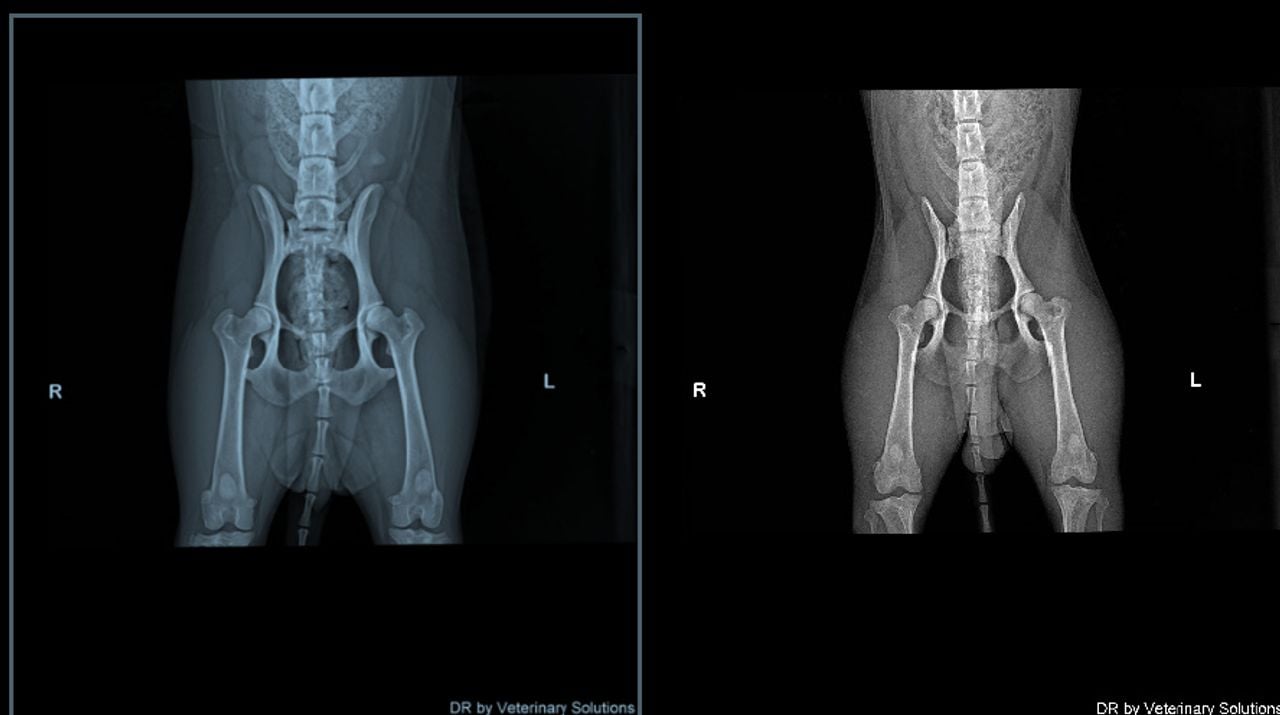

De start van puppy Jipp verliep goed, al vielen Eriks meteen wel een paar dingen op. “Onze hond stonk enorm toen we haar mee naar huis namen”, vertelt hij. Toch bleek Jipp bij een controle door hun eigen dierenarts gezond. Tot een paar weken later Eriks tijdens het uitlaten van de hond een knakkend geluid vaststelt. “Röntgenfoto’s toonden aan dat Jipp slecht ontwikkelde heupen heeft en dat ze een heupkom mist. Dit terwijl de fokker had gezegd dat haar ouders röntgenologisch getest waren en niets mankeren.”

Toen Eriks met zijn bevindingen naar de fokker ging, kreeg hij te horen dat ze Jipp mochten terugbrengen. “Dat doe je natuurlijk niet, Jipp was al vanaf de eerste dag onderdeel van ons gezin en het voelde niet goed om haar terug te brengen naar deze fokker.” Ook vroeg Eriks de foto’s op van de moeder en vader van Jipp. Na weken wachten ontving hij deze. “Het kon de moederhond van onze hond helemaal niet zijn. De foto’s zijn een aantal weken voor Jipp’s geboorte gemaakt, en de zogenaamde moederhond op de röntgenfoto’s was niet drachtig.”